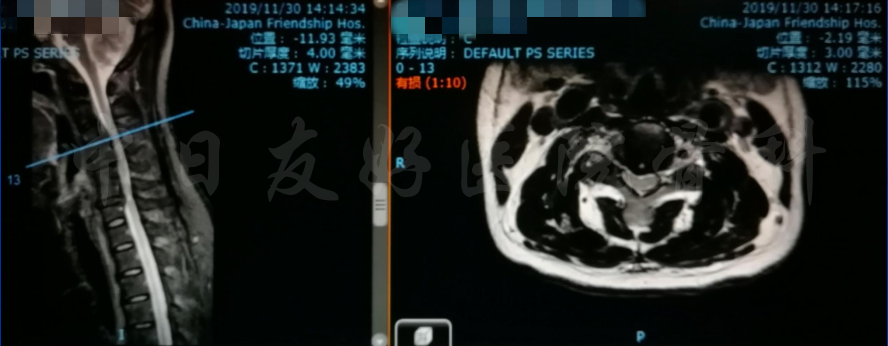

MRI

MRI颈4-5(左)、颈5-6(中)颈6-7(右)

矢状位MRI

轴位MRI:腰3-4(左)、腰4-5(中)、腰5骶1(右)

2019年11月30日 颈椎MRI提示:颈3/4颈4/5颈6/7椎间盘突出,椎管狭窄;颈5-6水平脊髓异常信号,变性可能。

颈椎MRI

颈椎MRI

颈椎各节段MRI(上下滑动)

腰椎MRI